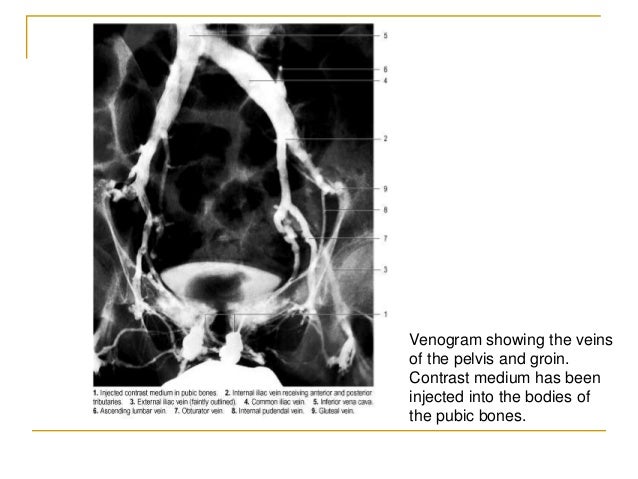

Viewing Playlist: Pelvis | Radiopaedia.org

radiopaedia pelvis